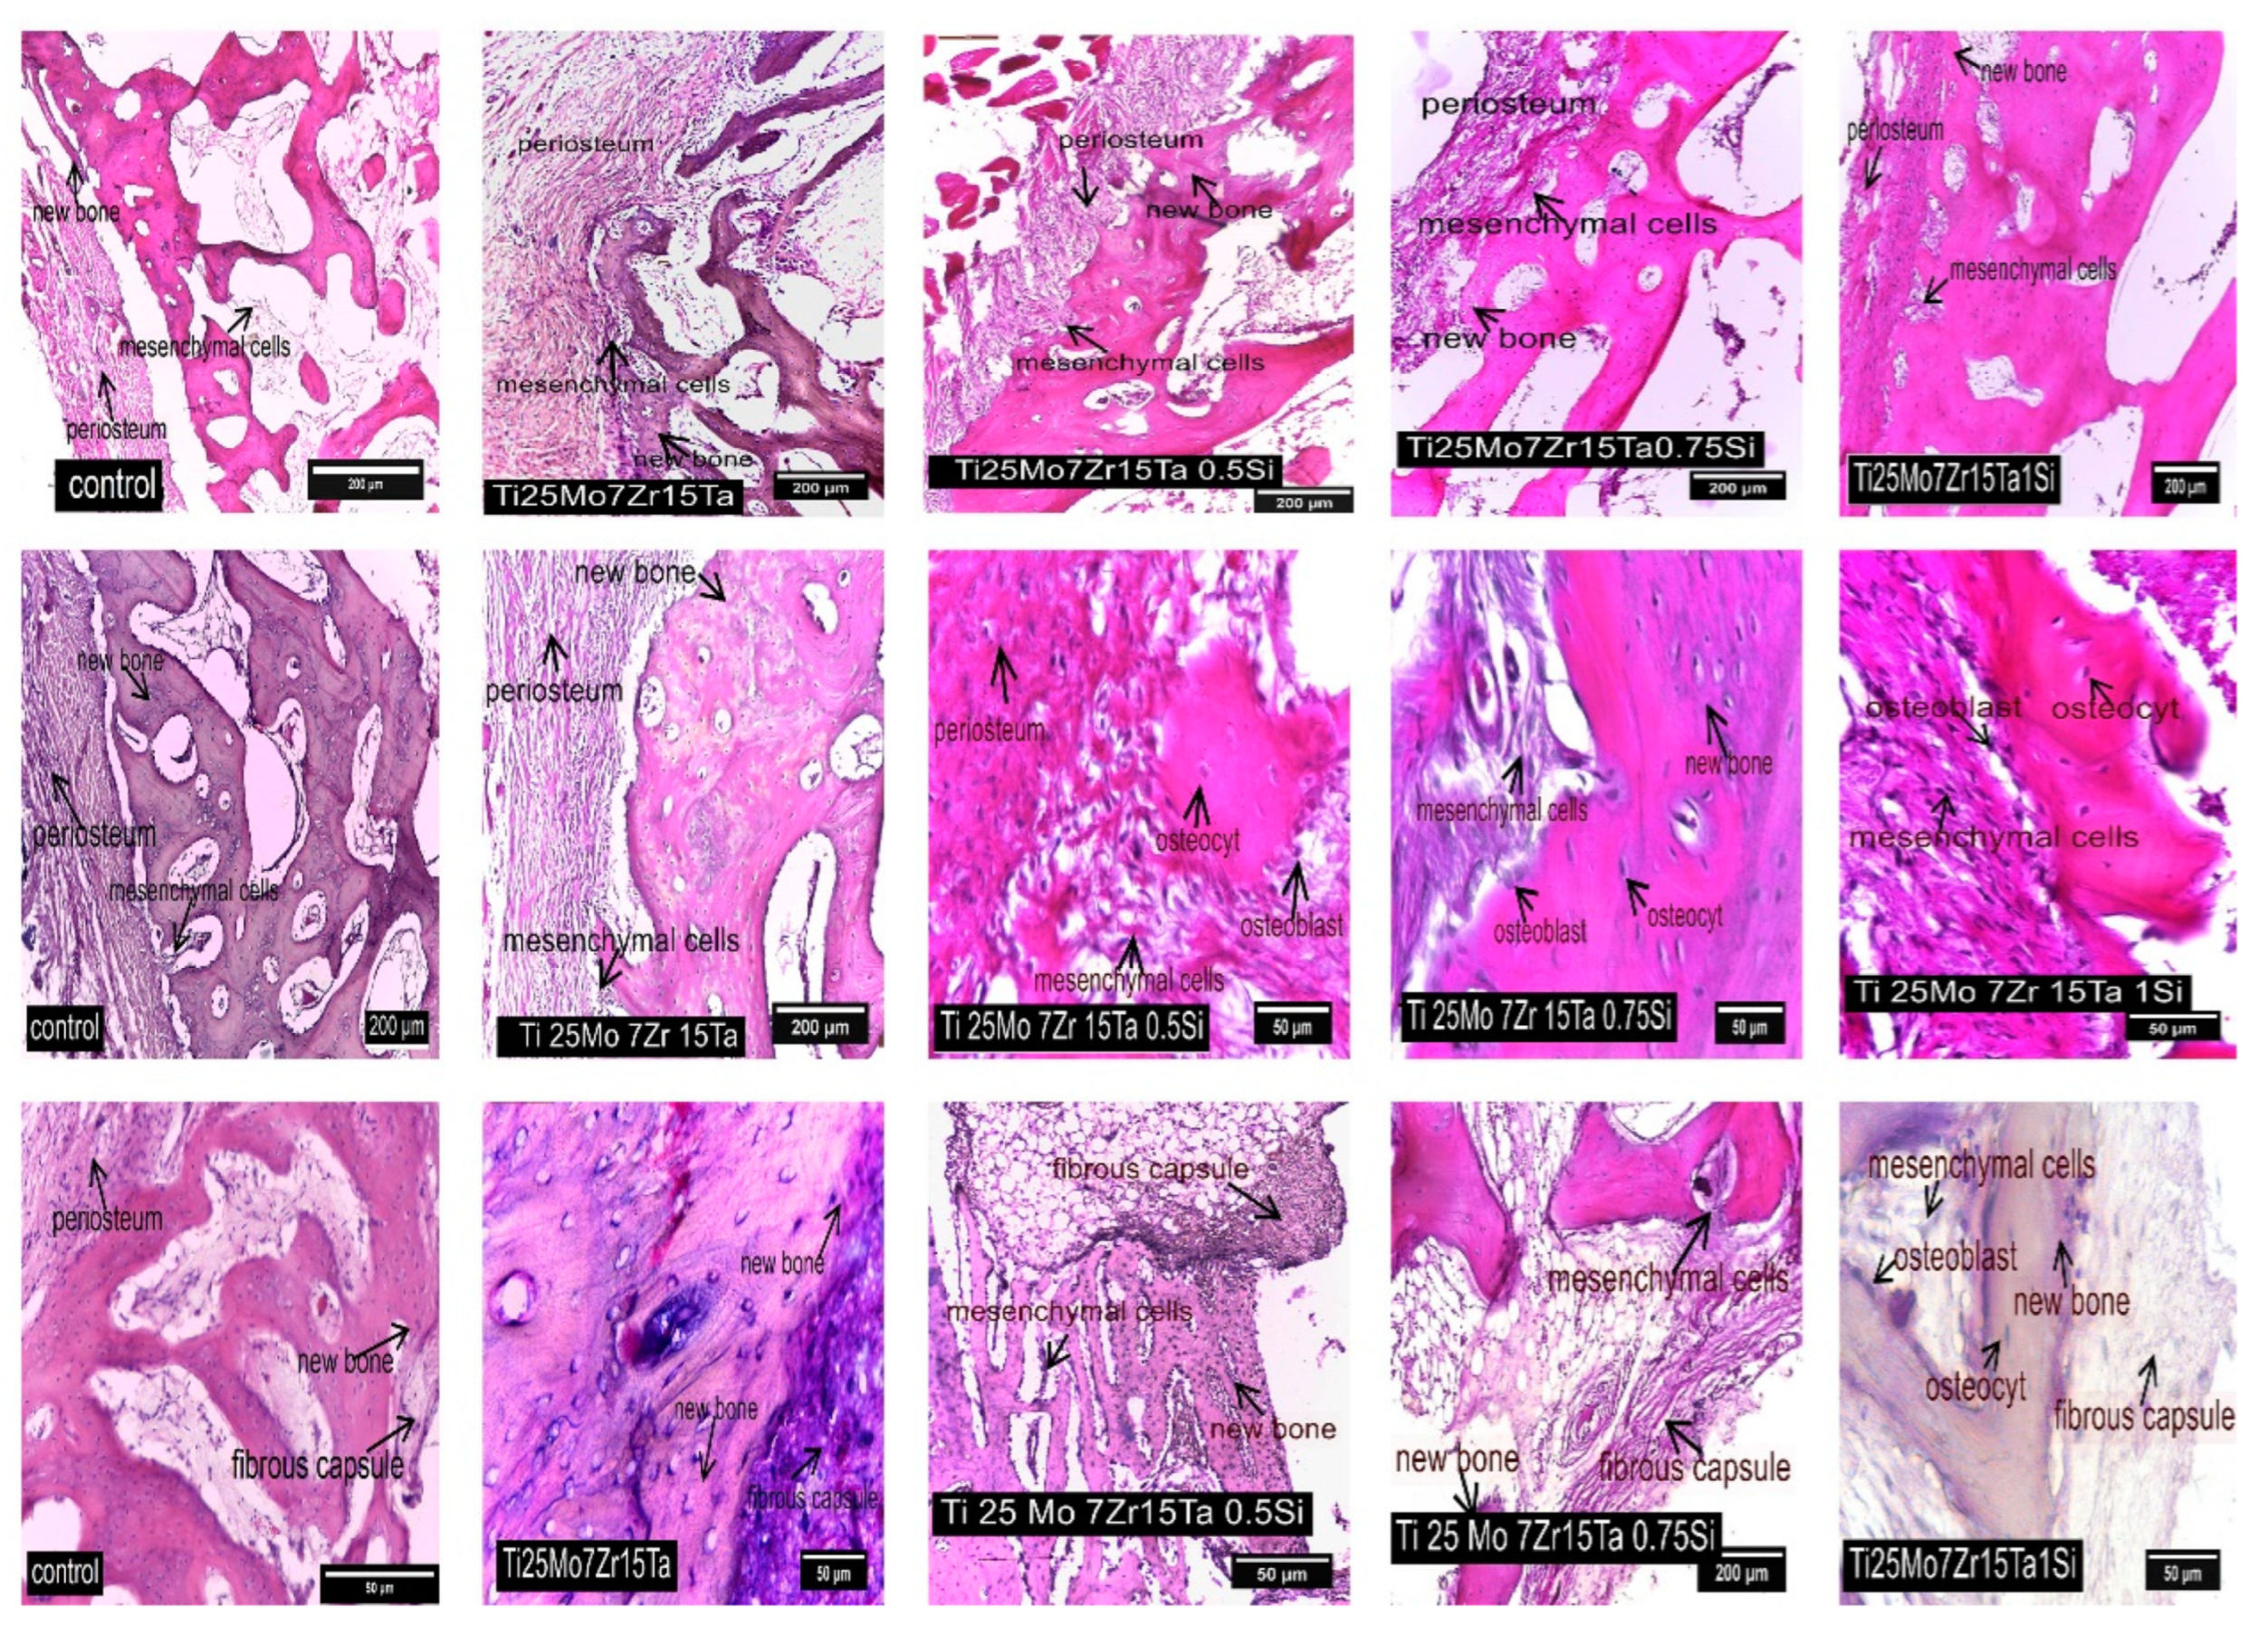

3.3. Interpretation of Results, Radiographs and Micrographs